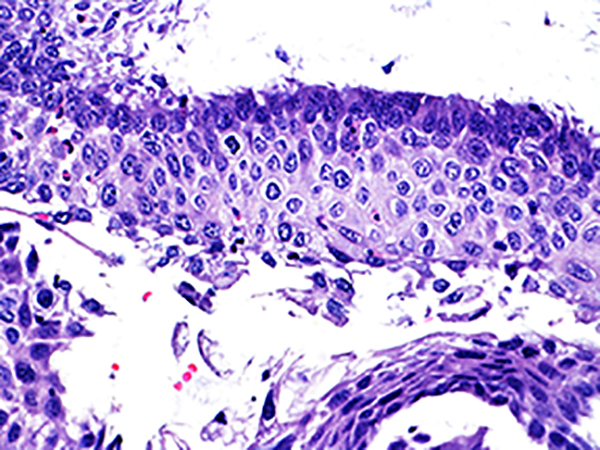

Area 2 - Soft Bx CIN 2 40x - High Power |

![]() Case 2